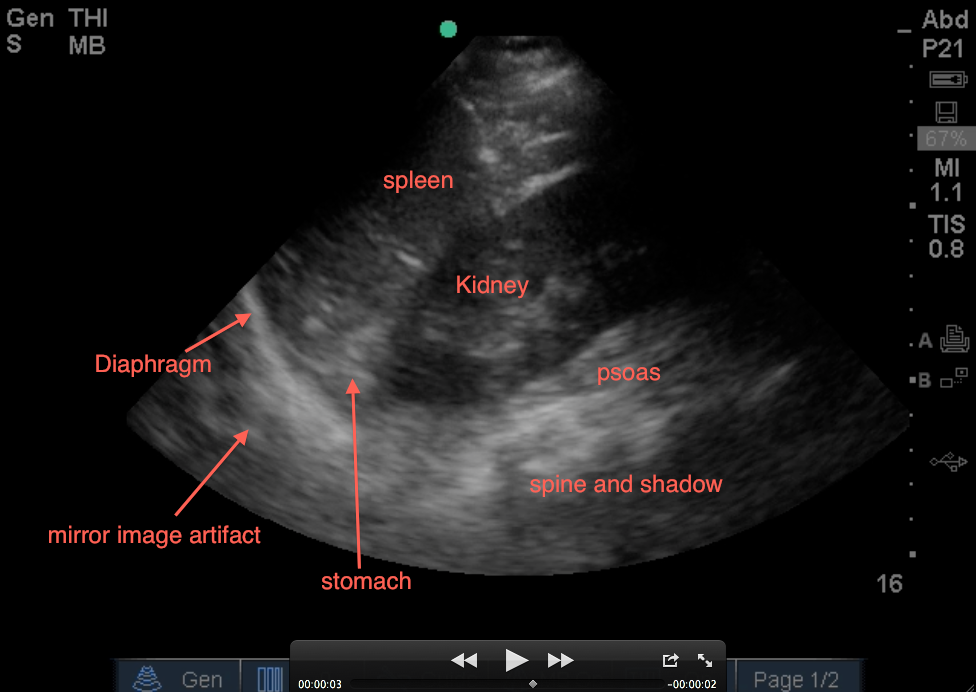

Let’s get into the LUQ view: First, assess that your probe is in the correct location by seeing (from top of screen to bottom): the spleen on your screen and slowly angling it posteriorly to get the kidney also on your screen which is right above the psoas and then spine (with it’s shadow). If you do not see the spleen, you may be too high or too low – slide down or up a rib space to get yourself oriented to the correct region with the depth usually being at 13-16cm using your phased-array low frequency probe.

1. Evaluate above the diaphragm…. to evaluate for intrathoracic free fluid. This may involve having to increase your depth while you slowly fan your probe anterior to posterior (from 13cm to 16cm – you dont usually need to go 19cm unless it’s a huge spleen). The patient’s breathing will also help you as you will notice the bright white (echogenic) linear diaphragm which hugs the spleen will move (right and left) on your screen with every breath. Having the patient take a deep breath and holding it, will allow you better visualization if a rib shadow is in your way. A mirror image of the spleen may be seen above the diaphragm (a normal artifact that occurs when ultrasound passes through structures of varying densities and then through air (lung). However, in the LUQ, If no mirror image, it may not mean free fluid, especially if the stomach is in your view. If the area above the diaphragm is truly anechoic (black) without Stomach Sabotage – that’s fluid in the thoracic cavity! The spine sign will also help you evaluate for free intra-thoracic fluid, as the spine and it’s shadowing normally stops once it hits the diaphragm when visualizing on the screen from right to left (air is the enemy of ultrasound!). But if there is fluid in the thoracic cavity, you will see the spine continue to traverse past the diaphragm up into the thoracic area (fluid is the lover of ultrasound!).